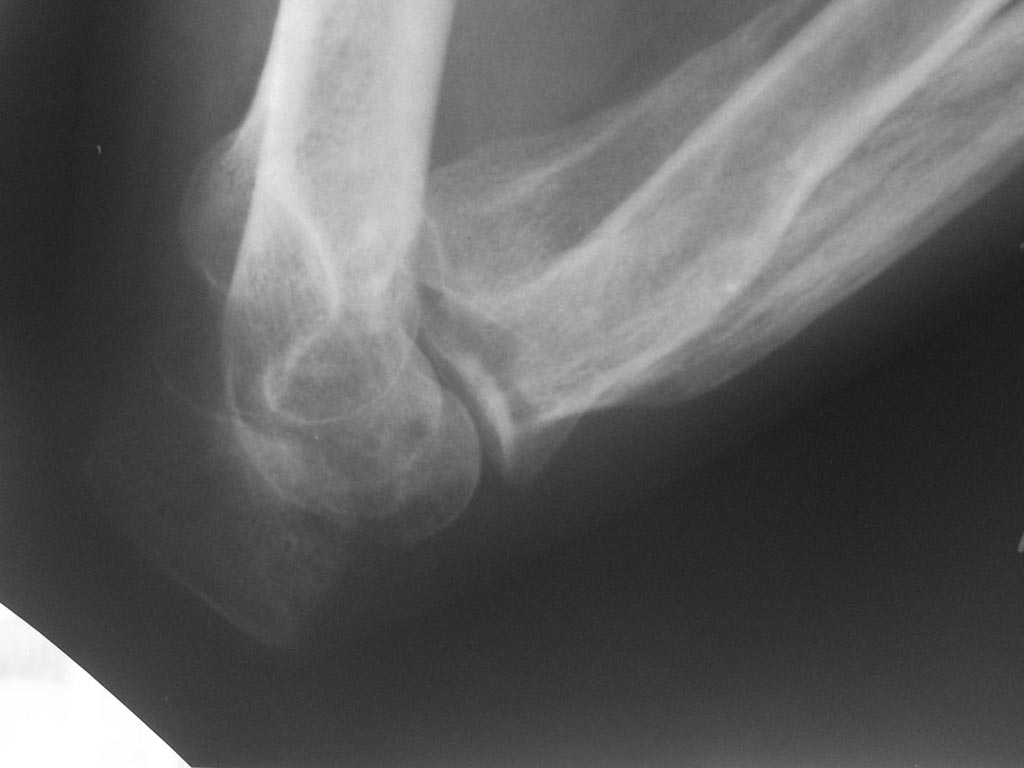

Лечения не было. Сейчас - контрактура и резко выраженный болевой синдром, в т.ч. вследствие давления trohlea humeri изнутри на кожу.

Качество первых двух снимков очень плохое. А на двух последних, по моему, перелом локтевого отростка. Если так, то просто остеосинтез

Локтевого отростка и передней стенки локтевой кости

Кроме КТ бывают обычные стандартные рентген-снимки, боковой проекции у Вас нет, потому и не знаете, как поступить с этим переломом локтевого отростка.